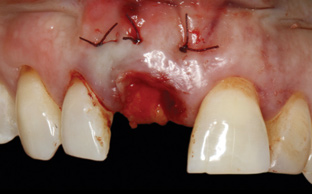

A 56-year-old female patient was referred for the evaluation of tooth No. 8 (Figure 4 and Figure 5). A periapical radiograph indicated that the tooth had undergone apicoectomy and received an excessively long post (Figure 6), and a cone-beam computed tomography (CBCT) scan of the site revealed a lack of buccal plate bone (Figure 7).

4. Facial and occlusal views of initial clinical presentation of tooth No. 8.

Figure 4

5. Facial and occlusal views of initial clinical presentation of tooth No. 8.

Figure 5

(6.) Pretreatment periapical radiograph.

Figure 6